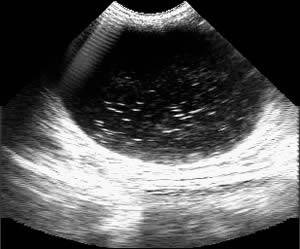

Визуализация мочевого пузыря

Мочевой пузырь – полый мышечный орган, предназначенный для скопления периодического выведения мочи. Соответственно наполненный мочевой пузырь является идеальным акустическим окном, поэтому: состояние стенок а также содержимое мочевого пузыря, имеющее диагностическое значение, может получить ультрасонографическую оценку. Диагноз «песок в мочевом пузыре» имеет право на существование – при этом визуализируются частицы 1-2 мм в диаметре (Эхограмма 2, рис. 2).

Эхограмма 2 |

РИС 2.А – мочевой пузырьВ – солевые частицы |

Однако «песок в мочевом пузыре» необходимо дифференцировать от воспалительной взвеси и это возможно сделать изменив положение животного. Вы увидите, что воспалительная взвесь, оседая в наиболее низко расположенных отделах, не дает акустической тени и имеет вид слизистого осадка или хлопьевидных мало подвижных сгустков. (Эхограмма 3,4, рис. 3,4).